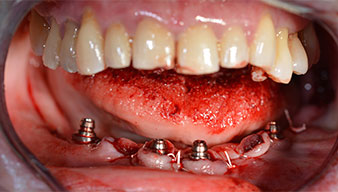

È stato avvitato un moncone angolato di 35 gradi per compensare la divergenza degli impianti distali. Ne risulta un profilo globale degli impianti situato il più perpendicolare possibile al piano occlusale. Questa situazione è un prerequisito per il posizionamento occlusale di protesi provvisorie e, successivamente, di quelle definitive (Fig. 15 e 16).

Successivamente, sono state prese le impronte e il morso di costruzione della paziente, per consentire al tecnico dentale di iniziare a realizzare la ricostruzione provvisoria. Quest'ultima è stata innestata lo stesso giorno (Fig. 17 e 18).

che aumenta il contrasto nella cavità orale e migliora la percezione visiva. Sia il contrangolo che il manipolo S-11 di W&H sono raffreddati esternamente, che rappresenta un enorme vantaggio perché la soluzione salina arriva esattamente dove è necessaria e può essere regolata se necessario. Contrangolo e manipoli sono smontabili e questo passaggio è caldamente raccomandato per motivi di igiene e sterilizzabilità. Sono stati posizionati quattro impianti SKY della misura di 4 x 14 mm.